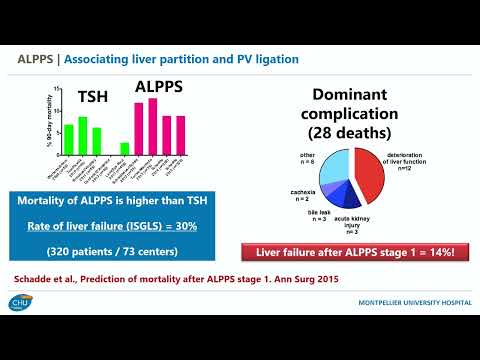

DEB04: Failed PVE ALPPS vs Hepatic Vein Embolization

Debate 04: Failed PVE ALPPS vs Hepatic Vein Embolization